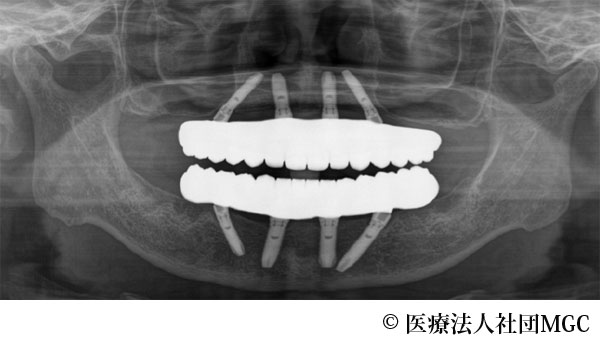

【症例1】上下All-on-4(オールオンフォー)

- 治療前

- 治療後

- 治療名

- 上下All-on-4(オールオンフォー)

- 費用

- 5,915,800円(税込)

- 期間

- 8ヵ月

治療内容

患者様の症状

歯がボロボロで食事が困難であるとご来院されました。

治療法

ご相談の結果、患者様の生活の質(QOL)を向上させ、しっかり噛めるように上下All-on-4(オールオンフォー)を行いました。

治療結果

機能性、審美性ともに改善し、満足していただけました。

※治療結果は患者様によって個人差があります。

治療を行う上での注意点(リスク・副作用)

インプラント周囲炎の可能性、まれに歯が欠ける可能性があります。